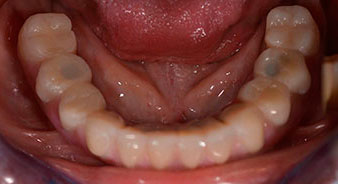

Para compensar la divergencia de los implantes distales, se atornillaron pilares acodados (35 grados) de forma que los perfiles de emergencia de todos los implantes quedaran en la posición más vertical posible en relación con la mordida. Este paso es necesario para poder atornillar de forma oclusal el tratamiento provisional y, posteriormente, el definitivo (figs. 15 y 16).

Tras esto, se realizan la impresión y el registro de la mordida para que el protésico dental pueda empezar inmediatamente con la elaboración de la prótesis provisional, cuya implantación se realiza el mismo día (figs. 17 y 18).

Una vez transcurrido el tiempo necesario para la integración ósea, puede llevarse a cabo la impresión definitiva del implante para realizar la prótesis definitiva de manera acorde (figs. 19 y 20). En este paso, el responsable del tratamiento y el paciente pueden decidir conjuntamente si es preferible un revestimiento cerámico o plástico y una estructura de zircón o de metal. En este caso, dado que el pronóstico de la dentición del maxilar superior era poco claro y la pieza dental 24 estaba elongada, el equipo del Dr. Pascu se decidió por un revestimiento de plástico, ya que, por lo general, es mucho más fácil de ajustar y puede adaptarse a la nueva situación del maxilar superior.